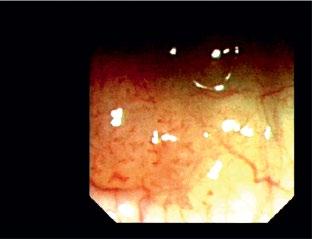

While applying PDT treatment of advanced lung cancer, it was observed that invisible small lesions in the bronchial mucosa became visible due to HPD fluorescence. This proved useful for detection of so-called early lung cancer, that is, in patients with positive sputum cytology with radiologically invisible lesions that could potentially be cured. In further studies, it was shown that by illumination with special light sources, the bronchial mucosa fluoresced without activation by HPD and several systems have been developed in fiberscopes and videoscopes for detection of early cancers by autofluorescence

As autofluorescence was unspecific for diagnosis of malignancy, methods for further analysis were added. Magnifying videobronchoscopes allow more detailed analysis of intra- and subepithelial structure, especially pathological vessels, that are characteristic of development of early bronchial cancer. By selecting smaller spectra in RGB imaging, narrow band imaging (NBI), the visualization of characteristic pathological vessels could be markedly improved. Further increase of resolution toward almost microscopy level could be achieved by EOCT in which an optical scanning beam is reflected from the different layers of the mucosa, providing optical histology images. The most recent technology, confocal microendoscopy, is finally bringing optical resolution to the cellular level [37].

1.10 Early lung cancer. The slight discoloration on white light becomes very prominent by autofluorescence (a). By magnifying endoscopy, the pathological vascularization becomes visible (b), which is even more prominent under NBI (c). In the EBUS image, the superficial lesion ventrally is thickened (3 mm) compared to the normal wall on the left (1.4 mm), but well within the confines of the bronchiall wall and can be treated by bronchoscopic intervention (d).